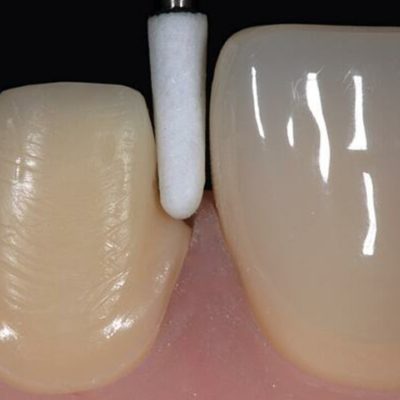

Культя зуба это

Культя зуба это 106 фото